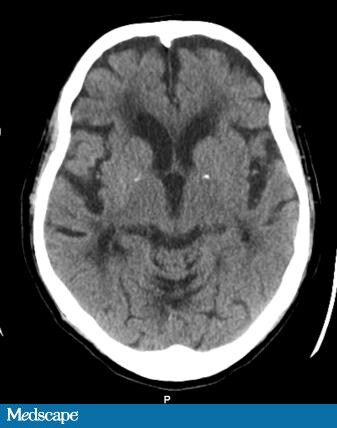

Cerebral diseases

Cerebral diseases 104 фото